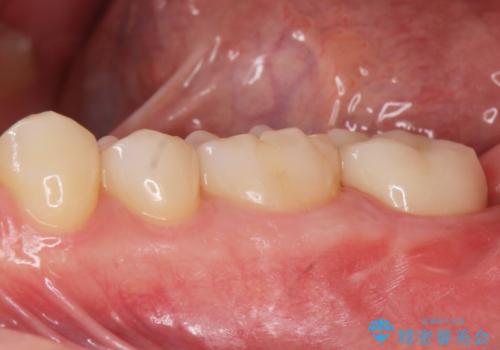

他院での治療に不信感 虫歯除去後のジルコニアクラウン

神経をとる処置をされた形跡がありましたがまだ虫歯が残っていたので全て取り除き、壁を立てて根管治療ができる状態にして、根管治療・ジルコニアクラウンで治療を行いました。

- ジルコニアクラウン・仮歯 12.1万円 根管治療(イニシャル)・ファイバーコア 13.2万円費用は治療当時の料金となります

虫歯除去、根管治療は拡大鏡やマイクロスコープを用いて治療を行っています。